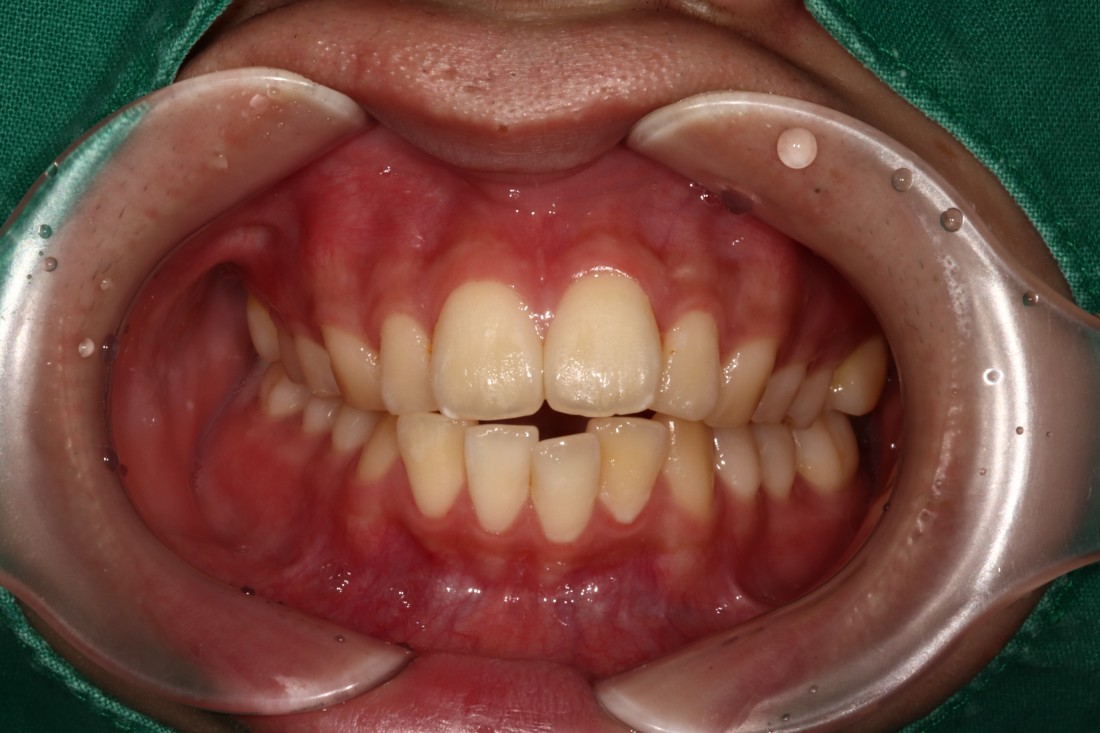

광주 개방교합 교정을 위해

방문해주신 30대 남성 환자분의

교정 전 사진입니다.

어금니를 맞닿게 하여서 입을 다물어도

윗니와 아랫니가 만나지 않는데요.